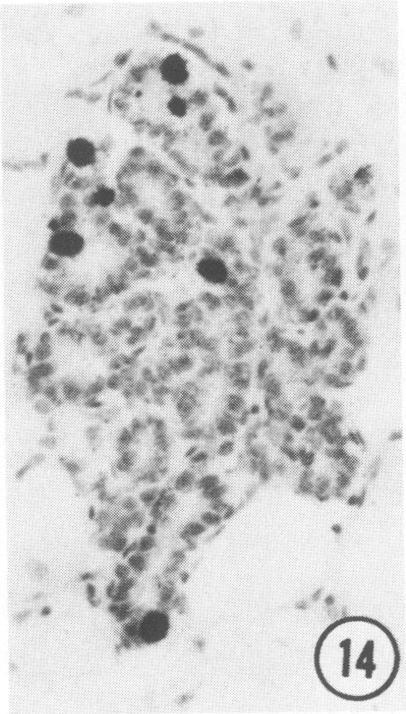

The influence of age and mammary gland differentiation on the incidence of tumors induced by 7,12-dimethylbenz(a)anthracene (DMBA) was studied by correlating the development of the mammary glands of 20-180-day-old, virgin Sprague-Dawley rats with the number and type of tumors induced by DMBA administered at those various ages. The number of terminal end buds (TEBs), terminal ducts (TDs), and alveolar buds (ABs)/sq mm and their DNA-labeling indices (DNA-LI) were determined. Highest density of TEB occurred when the rats were 20 days old, decreasing thereafter. DNA-LI ranged between 25.2 and 29 in TEB of rats aged 30-55 days, which was coincident with the highest incidence of carcinomas. With aging, the number of TEBs and their DNA-LI decreased and the number of TDs and ABs increased, although with a low DNA-LI, which correlated with a lower incidence of carcinomas and higher incidence of benign lesions.

通过将20至180日龄处女斯普拉格-道利大鼠乳腺的发育情况与在不同年龄给予7,12-二甲基苯并(a)蒽(DMBA)诱导的肿瘤数量和类型相关联,研究了年龄和乳腺分化对DMBA诱导肿瘤发生率的影响。测定了每平方毫米的终末芽(TEB)、终末导管(TD)和腺泡芽(AB)数量及其DNA标记指数(DNA-LI)。TEB的最高密度出现在大鼠20日龄时,此后逐渐下降。30至55日龄大鼠的TEB中,DNA-LI在25.2至29之间,这与癌的最高发生率一致。随着年龄增长,TEB的数量及其DNA-LI下降,TD和AB的数量增加,尽管DNA-LI较低,这与癌的较低发生率和良性病变的较高发生率相关。